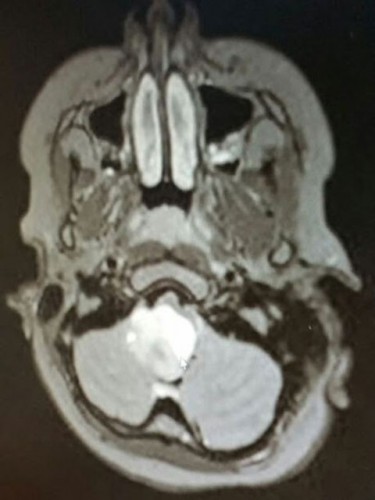

MR sonuçlarına göre 11 yaşındaki kızın beyninde tümör vardı. Acil bir ameliyatla beynindeki tümör alındı.